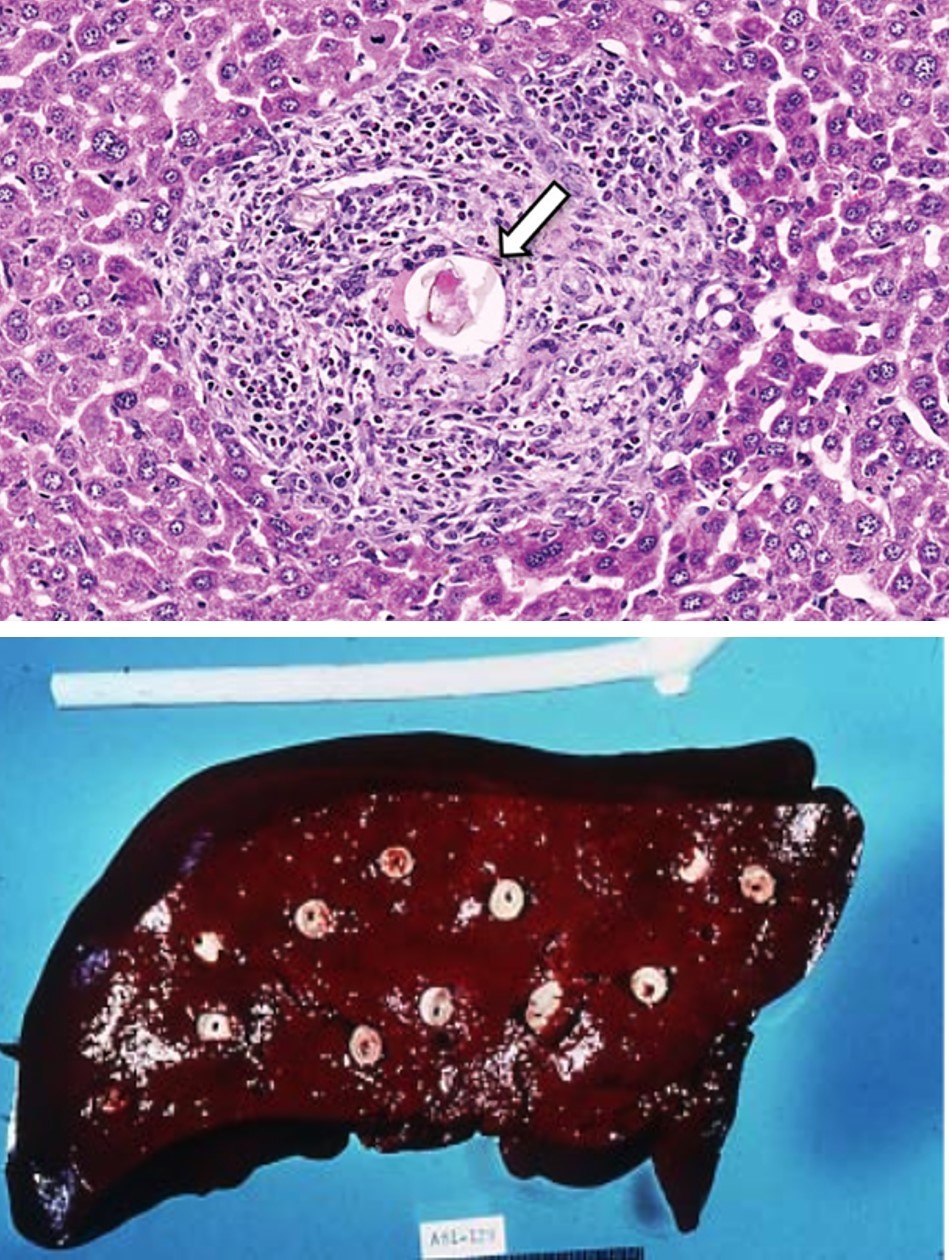

Schistosomiasis and Pipestem Fibrosis

Fibrin Ring Granulomas and Q Fever